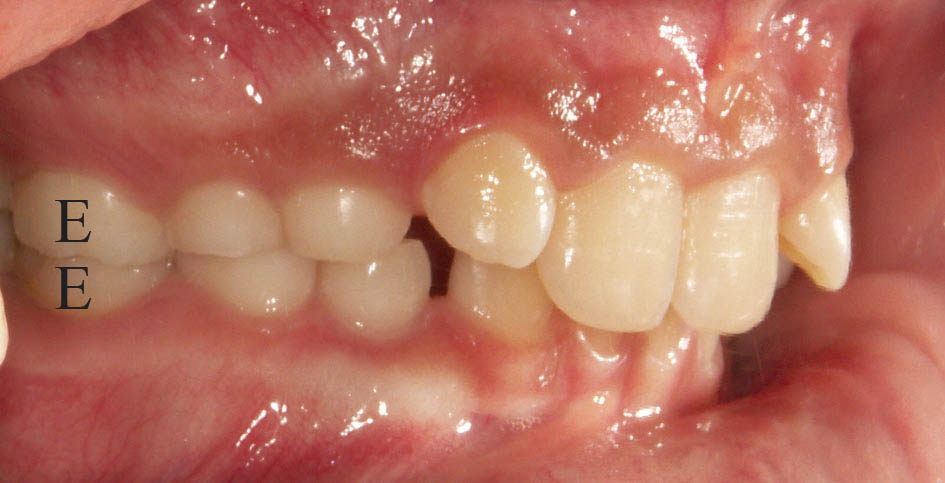

برای ارزیابی روابط افقی دیستال دندانهای E بالا و پائین را نگاه کنید.

اگر دیستال E پائین جلوتر از دیستال E بالا باشد (شکل 19-5) بیمار کلاسIII میشود. بعضی مواقع کلاسI هم میشوند.

اگر دیستال E پائین عقبتر از بالا باشد (شکل 20-5) بیمار حتماً کلاسII میشود.

اگر دیستال E بالا و پایین در یک راستا باشند احتمالاً کلاسI میشود (شکل 21-5). شاید عدهای از همین گروه در آینده کلاسII نیز بشوند.

شکل 19-5: دیستال E پائین جلوتر از دیستال E بالاست، لذا بیمار در آینده کلاسIII میشود

شکل 20-5: دیستال E پائین عقبتر از دیستال E بالاست، لذا بیمار در آینده به احتمال زیاد کلاسII میشود

شکل 21-5: دیستال دندانهای E بالا و پائین در یک راستا هستند